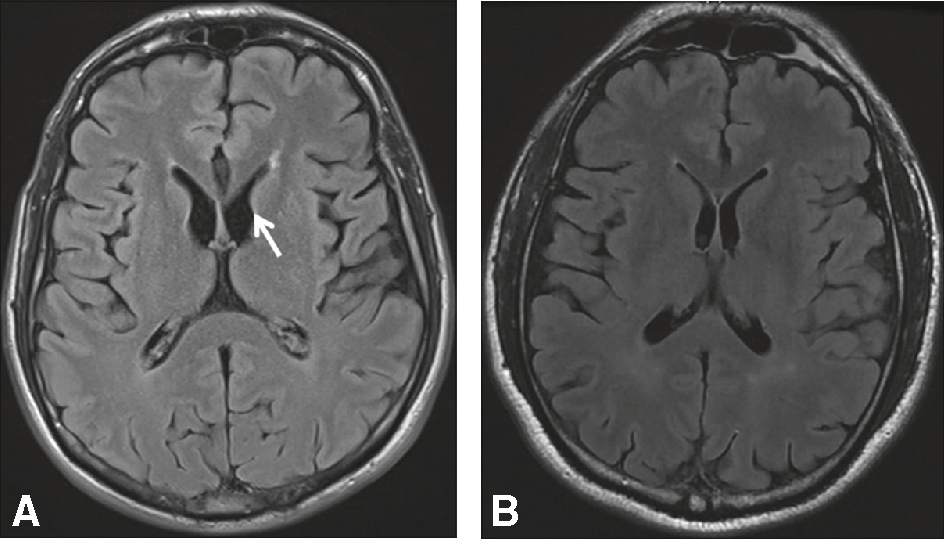

Figure Atrophie des noyaux caudés (fig. 18.3).

Fig. 18.3 Figure Maladie de Huntington. IRM cérébrale (séquence T2/FLAIR, coupe axiale).

A. Atrophie modérée du striatum gauche (flèche) dans une forme débutante. B. Patient contrôle.